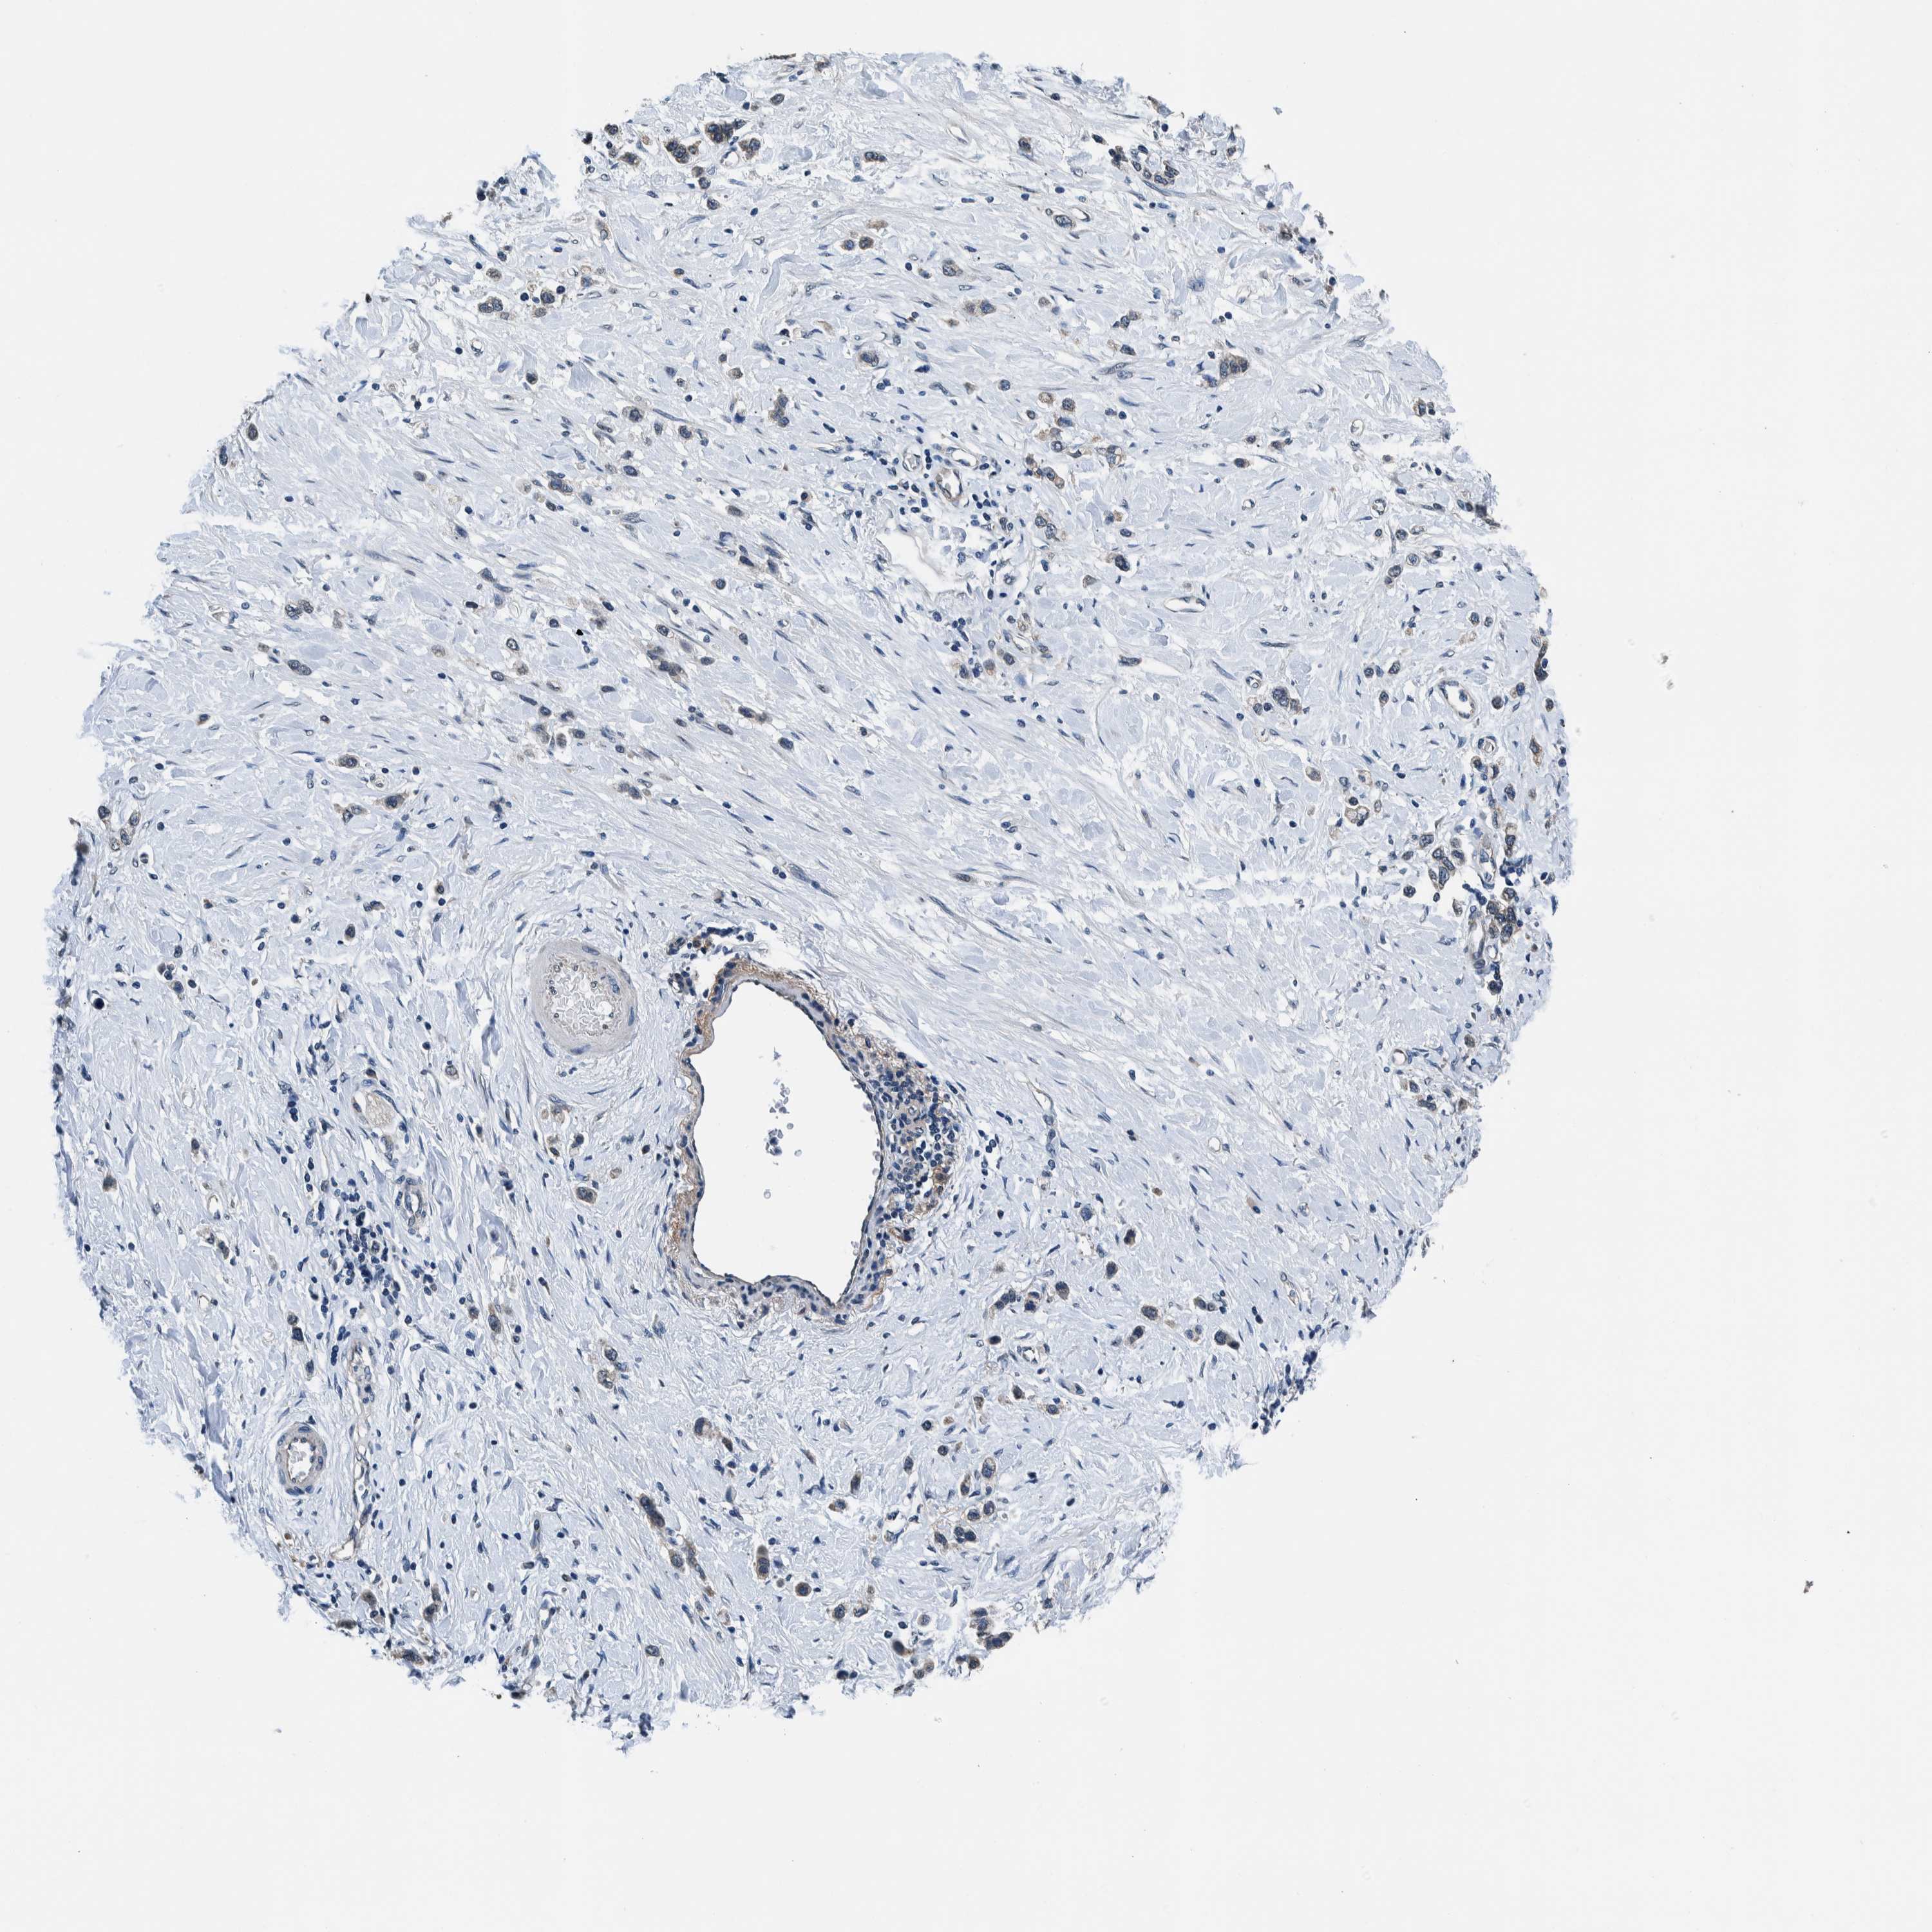

STOMACH CANCER - Protein expressioni

A mouse-over function shows sample information and annotation data. Click on an image to view it in a full screen mode. Samples can be filtered based on level of antibody staining by selecting one or several of the following categories: high, medium, low and not detected. The assay and annotation is described here.

Note that samples used for immunohistochemistry by the Human Protein Atlas do not correspond to samples in the TCGA dataset.

Antibody stainingi

Antibody staining in the annotated cell types in the current human tissue is reported as not detected, low, medium, or high, based on conventional immunohistochemistry profiling in selected tissues. This score is based on the combination of the staining intensity and fraction of stained cells.

Each image is clickable and will lead to virtual microscopy that enables deeper exploration of all samples and also displays staining intensity scores, fraction scores and subcellular localization as well as patient and tissue information for each sample.

Antibody HPA021284

Antibody HPA021417

Antibody HPA023261

Antibody HPA024312

Staining

High

Medium

Low

Not detected

Intensity

Strong

Moderate

Weak

Negative

Quantity

>75%

75%-25%

<25%

None

Location

Nuclear

Cytoplasmic/membranous

Cytoplasmic/membranous,nuclear

Adenocarcinoma, NOS